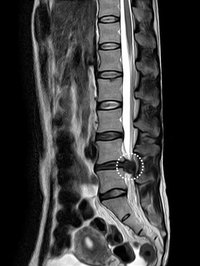

問診、診察で腰椎椎間板ヘルニアを疑ったら次に画像検査を行います。整形外科の基本の検査は単純エックス線写真ですが、残念なことに軟骨である椎間板はエックス線写真に写りません。そのためエックス線写真で腰の骨に異常がないことを確認した後、椎間板を直接観察できるMRI(磁気共鳴画像)検査を行います。写真のようにMRI検査で椎間板が突出している像を確認して腰椎椎間板ヘルニアと診断します。